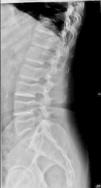

Caso clínicoVarón de 59 años con antecedente personal de diabetes mellitus tipo 2 en tratamiento con antidiabéticos orales, que acude a consulta de Reumatología por dolor inguinal bilateral y dorsolumbalgia de intensidad dolorosa progresiva, ambos de ritmo mecánico, que el paciente califica de muy intenso y que desencadenan dificultad progresiva para la deambulación; y por episodios de disnea de moderados esfuerzos, cuyo origen, estudiado por Neumología, era debido a dificultades en la expansión torácica. El cuadro doloroso no había presentado una respuesta satisfactoria a antiinflamatorios no esteroideos ni a opiáceos menores. En la exploración física se observa talla de 146cm, marcada cifosis dorsal, obesidad troncular, limitación importante para la flexoextensión y las rotaciones de ambas articulaciones coxofemorales, y braquidactilia en ambas manos. Hemograma y bioquímica sanguínea con valores normales. El estudio radiológico convencional de columna dorsolumbar, anteroposterior de pelvis y posteroanterior de manos se muestran en las figuras 1 a 4.

El paciente descrito presenta datos que sugieren una displasia espondiloepifisiaria tarda. Esta entidad tiene una herencia recesiva ligada al cromosoma X1, estando por lo tanto afectados sólo los varones. Se han descrito mutaciones en el gen SELD en el cromosoma Xp22.12-p 23.311. El diagnóstico se realiza entre los 5 y los 10 años de edad, cursando con enanismo de tronco corto; esto es, retraso en el crecimiento de la columna vertebral con una talla media final de 145cm y desproporción entre la longitud de las extremidades y el tronco2,3. La articulación coxofemoral está siempre afectada en coxa vara con aplanamiento leve de las epífisis, que conducen a cambios artrósicos precoces, y que pueden, en estadios más avanzados, incapacitar al paciente2–4. A nivel axial se describen cambios displásicos vertebrales con platiespondilia, que provocan cifosis progresiva4–6 con aumento del diámetro anteroposterior del tórax, y que en último término puede provocar episodios de disnea. No aparece retraso mental, se han descrito formas familiares con asociación a condrocalcinosis7,8 y existe una forma de displasia espondiloepifisiaria tarda asociada a artropatía degenerativa precoz, que puede simular artritis reumatoide juvenil9.